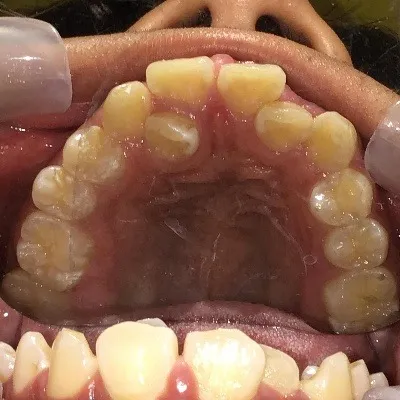

今回は他院さんでインビザライン矯正治療を受けていた患者様を引き継いで当院でインビザライン治療を継続した症例をご紹介致します。

今回はマウスピース矯正を主軸にした矯正ですが、一部ワイヤー矯正も併用して改善しております。

マウスピース矯正のみしか行っていない歯科医院では対処しきれない場合もあり、ワイヤー矯正とマウスピース矯正どちらも行える歯科医院で矯正治療を始めることがきれいな歯並びに近づける方法です。